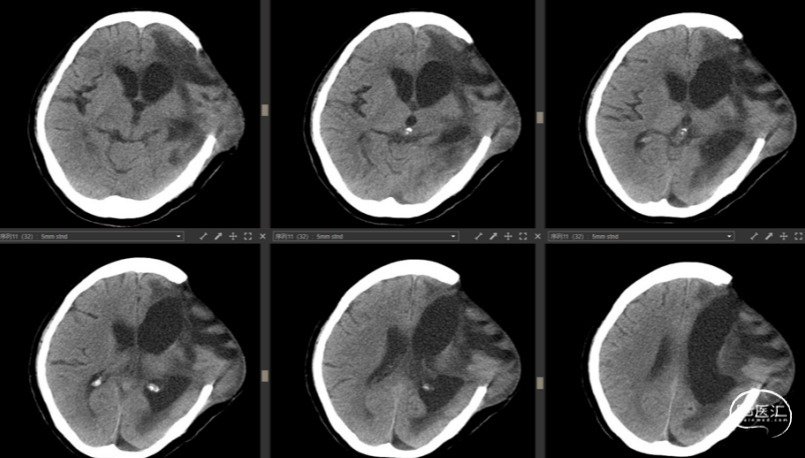

去骨瓣术前颅脑CT情况

去骨瓣术后颅脑CT情况